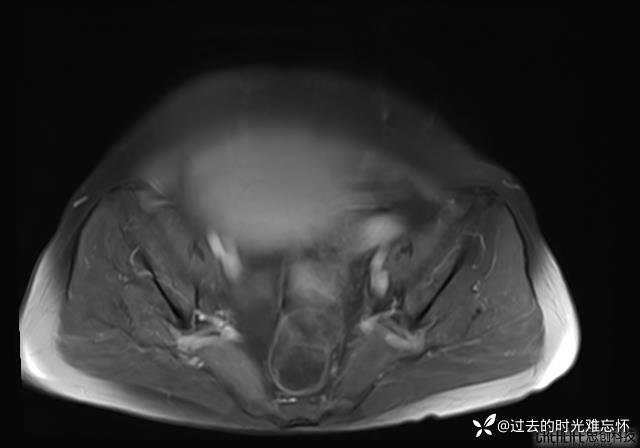

腹大能容5000液;术后腹部好轻松。妙手回春有结果。公布结果。

患者性别:女

患者年龄:65岁

主诉: 发现腹部隆起半年余。无其他明显不适。

浆液性囊腺瘤 (22)